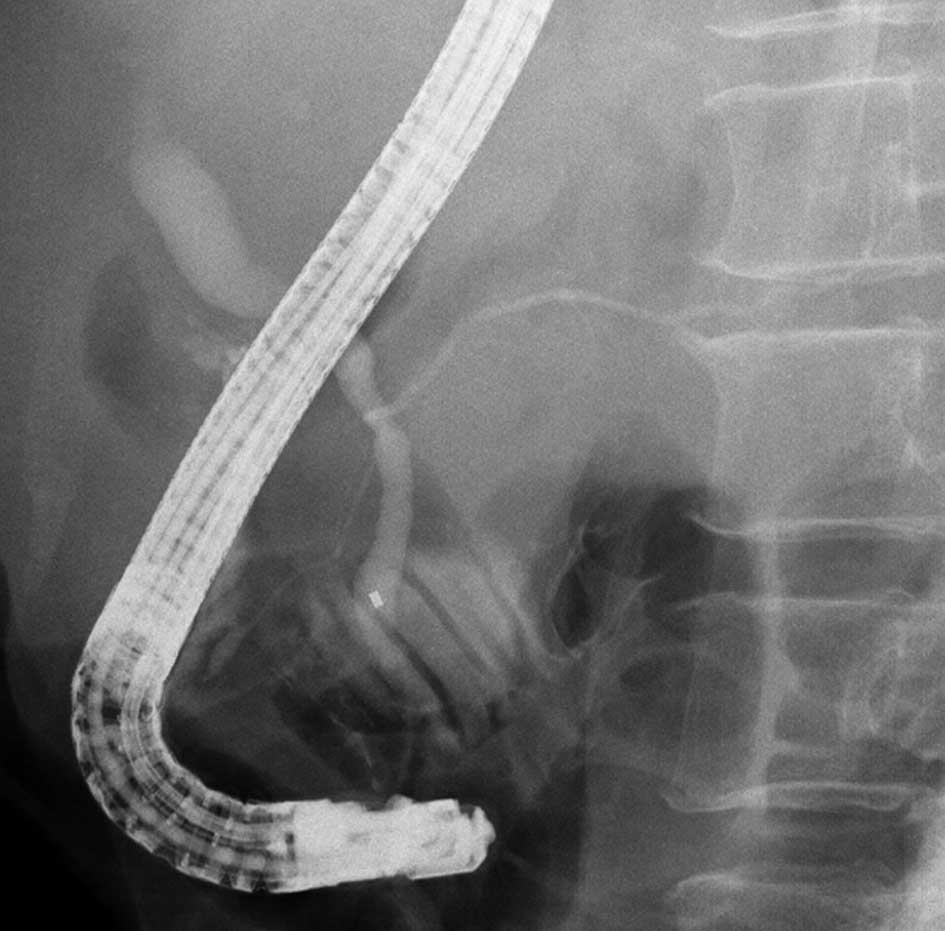

Figure 4.

Endoscopic retrograde cholangiography showing that the main pancreatic duct had joined the common bile duct.

Endoscopic biliary drainage and expandable metallic stent placement was performed for obstructive jaundice due to lymph node metastasis 23 months after beginning treatment. The patient was then diagnosed with pancreaticobiliary maljunction (Fig. 4). The patient succumbed to the disease due to the progress of cachexia 25 months after the first visit. An autopsy was performed, and the patient was diagnosed with locally advanced, poorly differentiated adenocarcinoma of the gallbladder with multiple liver, lung, lymph node, left ovary and skin metastases.